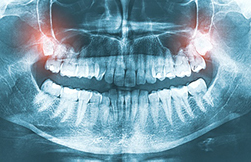

X-ray image of wisdom teeth. Have you ever heard the term "impacted tooth" and wondered what it actually means? Essentially, it describes a tooth that's stuck and unable to erupt fully into its proper position in your mouth. It's like a car stuck in the mud – it's there, but it can't move forward. Let's dive into what causes this and what it means for your oral health.